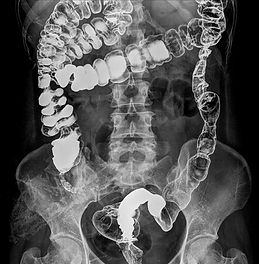

Colon hydrotherapy, also known as colonic hydrotherapy or colonic irrigation, is a safe and effective method of cleansing the large intestine using purified, filtered water. During a session, water gently flows into the rectum through a small, disposable nozzle, helping loosen and release waste material and gas. This process supports the body’s natural elimination system and can improve both colon health and overall wellness.

Some people wonder how colonics differ from enemas. While enemas cleanse only the lower portion of the colon, colon hydrotherapy can reach much farther into the large intestine, allowing a more complete detox. It also stimulates peristalsis, helping tone and retrain the colon for improved long-term function.